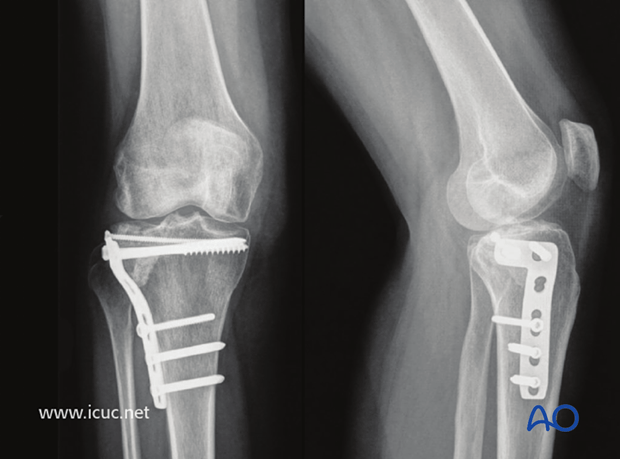

Szóval lelkiekben felkészített, hogy ez közel sem lesz egy egyszerű, hétköznapi műtét. Két lemezt és nyolc csavart kellett a térdembe juttatni. Általában térdműtéteket nem altatásban csinálnak, hanem epidurális érzéstelenítéssel (tehát a sérült ébren van, csak nem érez semmit deréktól lefelé). Viszont az én műtétem ehhez túl komplikált és hosszú volt, ezért mindenképp az altatásra szavazott a doki (három és fél órás volt a műtét, és közben forgatni is kellett engem). Őszinte leszek, nekem sem lett volna kedvem ébren lenni a műtét alatt, szóval én is az altatásra szavaztam.